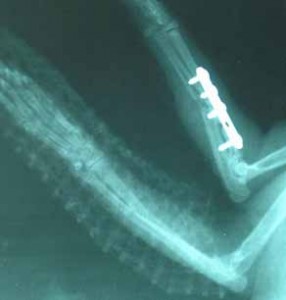

Dne 30.03.2006 se Sisi podrobila operaci, při které byla provedena osteosyntéza, kdy se tato těžká zlomenina fixovala šrouby. Druhou frakturu fixuje termoplastická dlaha. Sisi se po této těžké operaci velice dobře zotavila, hned začala baštit a cítila se dobře, takže naštěstí nebylo nutné kočičku zatěžovat infuzí.

Sisi RTG po operaci